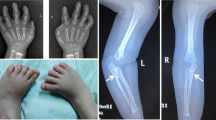

The child (II-2) (Fig. 2a) is the first male child of apparently healthy nonconsanguineous parents. The mother and the father were 33 and 45 years old respectively at the time of his birth. Fetal movements were poor. Routine ultrasound examination was normal until 23 weeks of gestation when bilateral radial agenesis was demonstrated. The child was born post-term at 43 weeks of gestation by normal vaginal delivery. Birth weight was 2810 g (10th-25th centile). He was admitted to our institute at 4 months of age. Physical examination showed good nutritional status, forehead and right cheek telangiectasia, scapulo-humeral hypoplasia, bilateral radio-ulnar agenesis with intact thumbs, bilateral proximal positioning of the first metacarpal, bilateral fifth finger clinodactyly and bilateral radial deviation of the hands. X-ray confirmed all these skeletal findings. The child also presented thrombocytopenia (40.000/mmc), PTT (43.7 s). The phenotypic features were characteristic of TAR syndrome (MIM 274000).

During the third pregnancy (II-3) (Fig. 1b), ultrasound examination was performed at 11 weeks of gestation, suggesting the presence of upper limb anomalies. This finding was confirmed at 15th week of gestation. The couple opted for termination of pregnancy. The chromosomal analysis of amniotic cells (400 bands) excluded any visible abnormality. Post-mortem examination of the fetus demonstrated bilateral radial agenesis (Fig. 2b). The mother had a previous pregnancy, which ended in spontaneous abortion at the 2nd month of gestation (II-1). There was no exposure to alcohol, smoking or infections during pregnancy. A subsequent pregnancy resulted in the delivery of a healthy child (II-4).